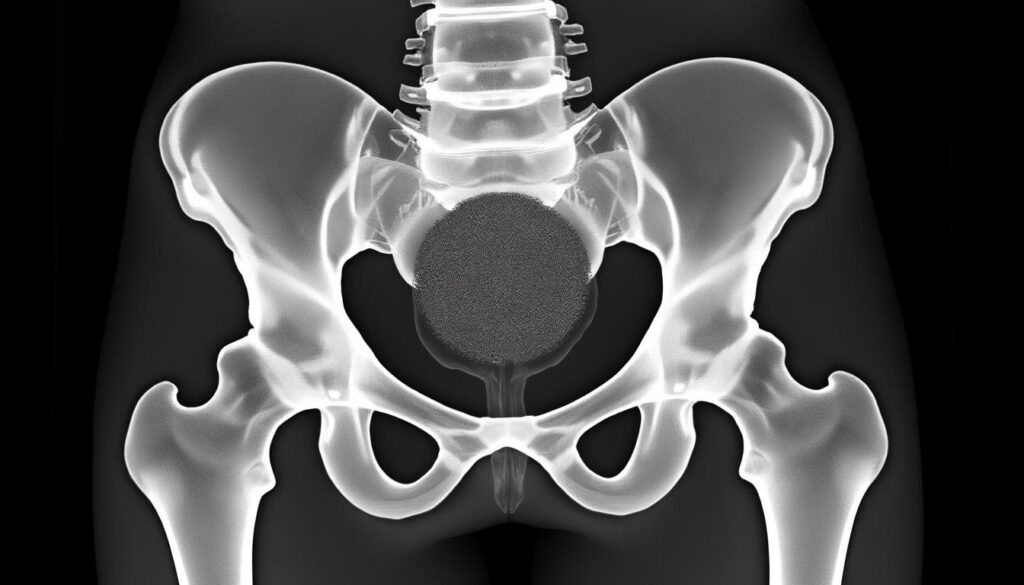

Métastase osseuse : comprendre la tache noire sur radio du bassin

La présence d’une tache noire sur une radio du bassin inquiète souvent, car elle peut indiquer une lésion osseuse suspecte. …